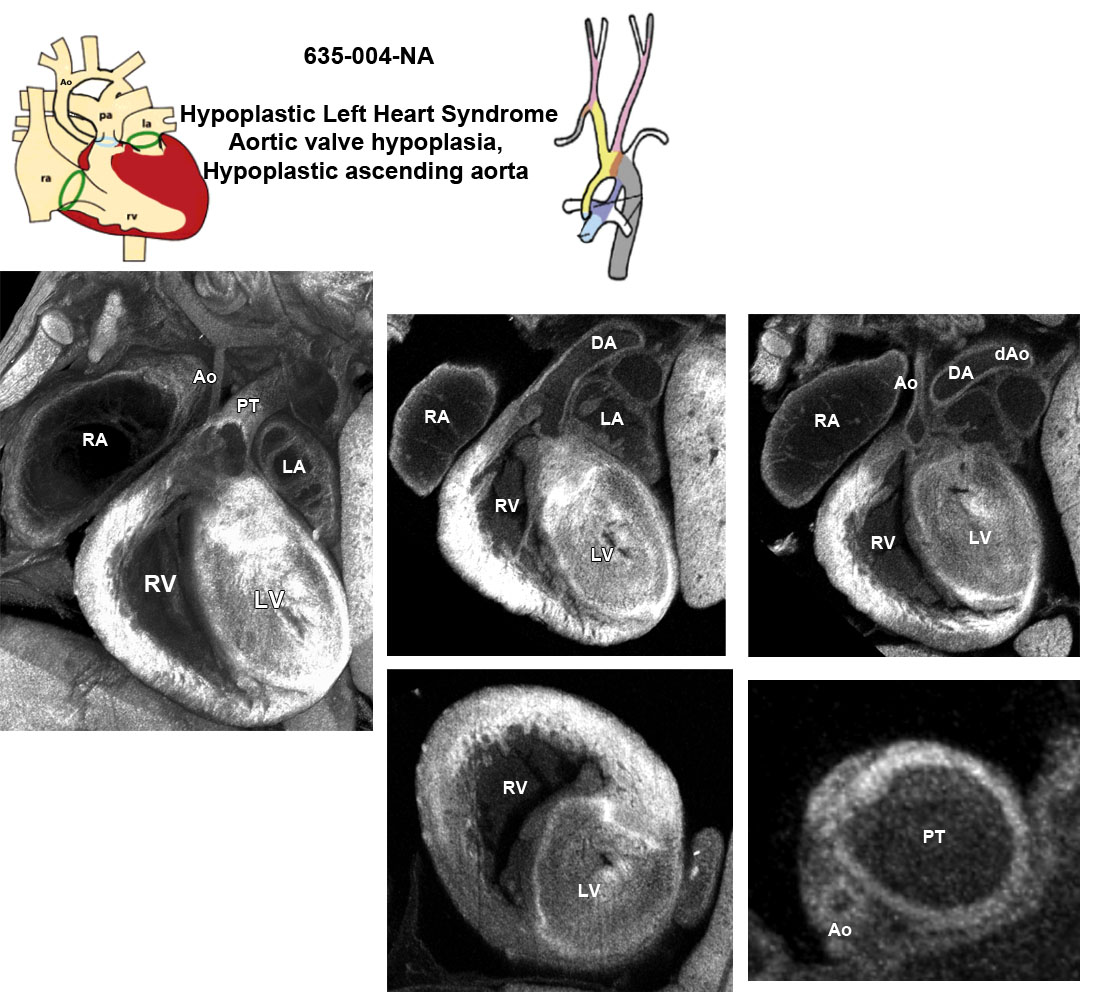

Caption EFIC Summary

Copyright This image is from the Laboratory of Dr. Cecilia Lo, a member of the Cardiovascular Development Consortium (CvDC), Bench to Bassinet (B2B) program of the National Heart Lung and Blood Institute (NHLBI), and is displayed with the permission of the authors. J:175213

b2b635Clo Mutant line 635; Bench to Bassinet Program (B2B/CVDC), mutation 635 Cecilia Lo

b2b635Clo/b2b635Clo C57BL/6J-b2b635Clo